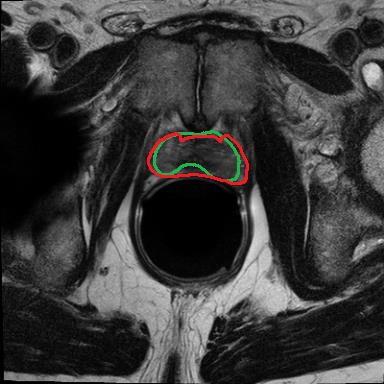

Modern deep neural networks struggle to transfer knowledge and generalize across diverse domains when deployed to real-world applications. Currently, domain generalization (DG) is introduced to learn a universal representation from multiple domains to improve the network generalization ability on unseen domains. However, previous DG methods only focus on the data-level consistency scheme without considering the synergistic regularization among different consistency schemes. In this paper, we present a novel Hierarchical Consistency framework for Domain Generalization (HCDG) by integrating Extrinsic Consistency and Intrinsic Consistency synergistically. Particularly, for the Extrinsic Consistency, we leverage the knowledge across multiple source domains to enforce data-level consistency. To better enhance such consistency, we design a novel Amplitude Gaussian-mixing strategy into Fourier-based data augmentation called DomainUp. For the Intrinsic Consistency, we perform task-level consistency for the same instance under the dual-task scenario. We evaluate the proposed HCDG framework on two medical image segmentation tasks, i.e., optic cup/disc segmentation on fundus images and prostate MRI segmentation. Extensive experimental results manifest the effectiveness and versatility of our HCDG framework.